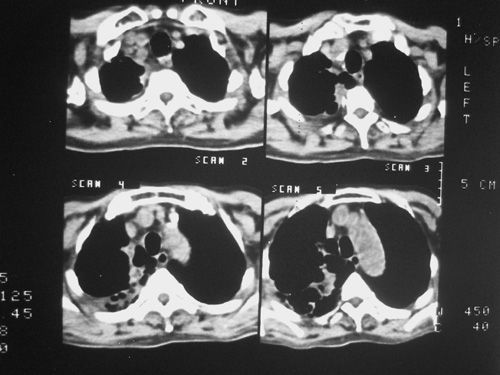

老年男性,70岁。煤矿工人20年。一周前咳嗽、发烧,拍x片考虑矽肺可能。始终咳嗽行ct检查,发现弥漫性病变,似感染但密度很高,细支气管肺泡癌无法排除,请老师给予指点。

一般矽肺多为双肺融合状,团块状高密度结节影.并散在多处小结节影.可这个病人只表现在单肺,并没有融合结节影.一周前的x片没显示大片高密度影,可定位扫描时(图象忽略传了),右肺已经清晰显示大片高密度影.作比较感觉是新病灶.可实际表现又不象,所以才拿来让各位老师看看.

ct片与平片只相隔1周时间变化太大,结合临床应该首先考虑尘肺合并感染,肺泡癌变化不会这么快,